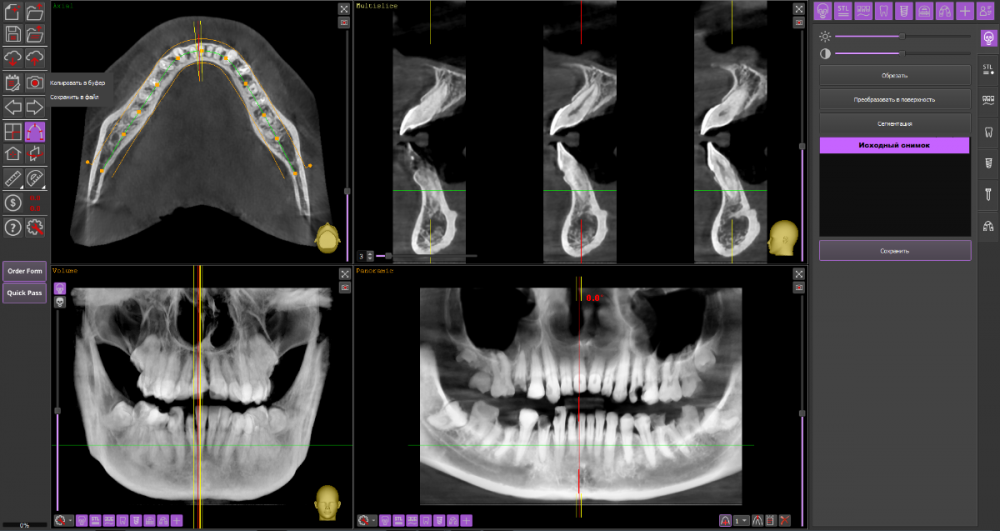

Множественные гранулемы и периодонтит зубов нижней челлюсти

Короткая предыстория. Мне 32 года. Около десяти лет назад мне сделали все зубы - преимущественно пульпиты на нижней челюсти и глубокие кариесы на верхней. Поскольку пломбы были очень объемными, меня предупредили, что по мере выпадения лет через пять нужно будет ставить коронки. Собственно, год назад они и посыпались, в основном вместе с остатками моих зубов. Я отправилась к стоматологу, чтобы поставить коронки на все зубы и впервые в жизни получить ровную белоснежную улыбку. Меня отправили на КТ и... Состояние нижней челюсти оказалось плачевным.

8-ки растут в 7-ки, на корнях 7-ок, 6-ок, 45, 4-ок, 3-ек и 42 периодонтит.

Сказали, что 6, 7, 8 на удаление, остальные можно попробовать пролечить, но долго и без гарантий. И воспалительный процесс может вернуться в любой момент, как и обостриться.

P.S. Программа-просмотрщик с диска КТ наотрез отказалась устанавливаться на мой компьютер. Как сделать панорамный снимок в radiant я не поняла. Других просмотрщиков я не нашла. Так что не обессудьте... Как смогла так наскринила.

Ссылка на архив КТ: https://drive.google.com/file/d/1gAqYmfxYKORXjXIwBrLFStw-nEyVh5Uu/view?usp=sharing